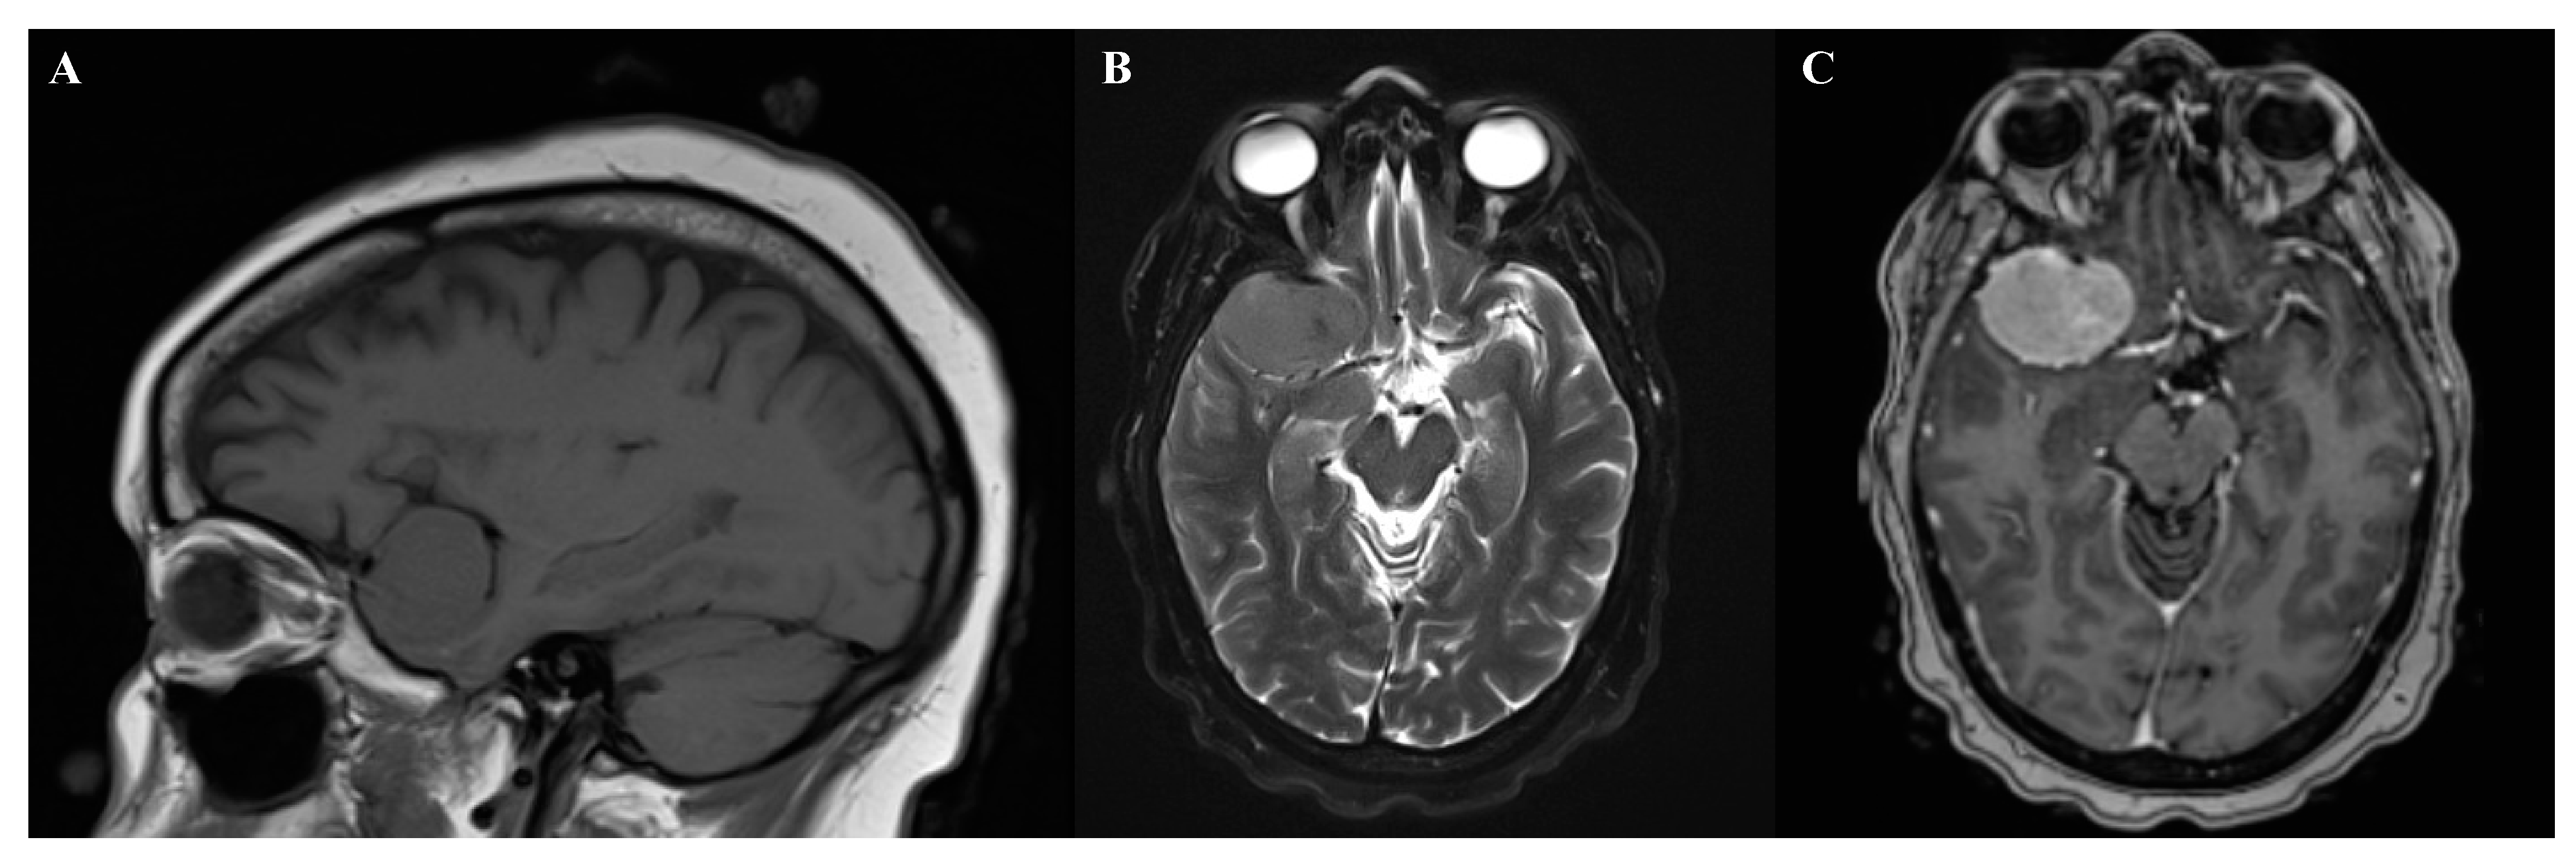

2.3. Diagnostics